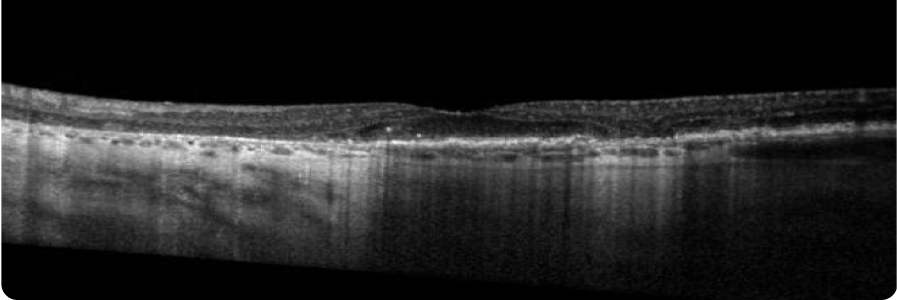

BASELINE VISIT

- BCVA: 6/9

- Visual function: Patient has dark adaptation issues and some difficulty reading

OCT

2 YEARS AFTER BASELINE VISIT

- BCVA: 6/12

- Visual function: Patient no longer feels comfortable driving although she is legally able to. Patient relies heavily on assistance from caregiver with some activities of daily living

Clear progression of perifoveal GA two years later.

Images courtesy of Mohammad Rafieetary, OD, Charles Retina Institute.